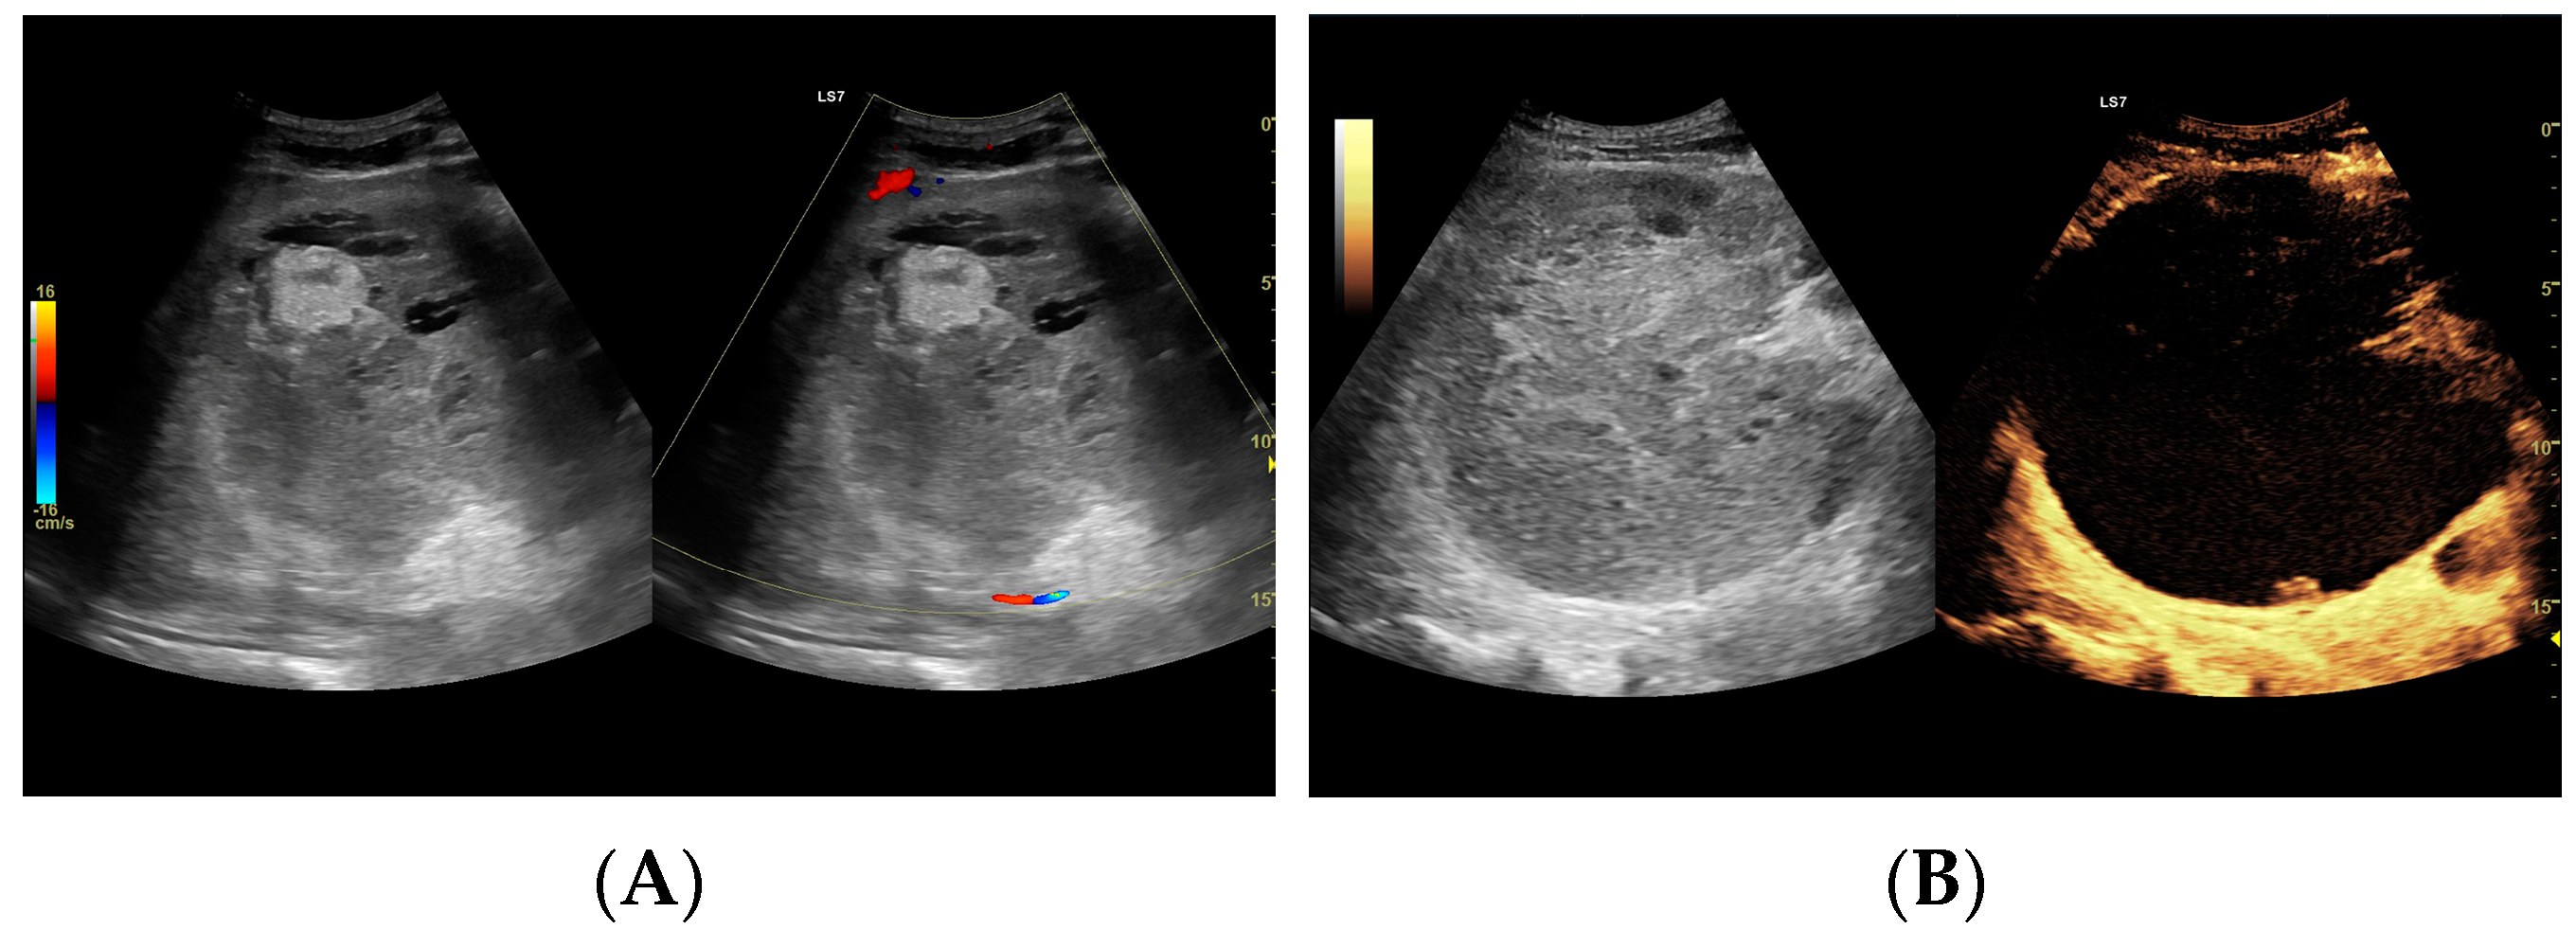

Figure 3.

(A) Ultrasound and color Doppler: The transverse view shows a focal lesion involving virtually the entire liver parenchyma, identified as a type I abscess. In B-mode, the lesion appears solid and heterogeneous, with small hypoechogenic foci that can be identified as fluid fragments. Confident classification of the lesion as a hepatic abscess based on these images alone is impossible, including accurate determination of the content and location of the fluid component. (B) CEUS arterial phase: The enhanced abscess capsule is clearly visible, with the purulent content occupying virtually the entire lesion. There is the possibility to assess the liquefied component of the abscess with high accuracy. The total abscess was estimated to be 191.25 cm² from CEUS, while the fluid fractions were estimated at 6.51 cm² on B-mode and 166.51 cm² on CEUS, respectively, which, according to the methodology used, translates to 104.42 mL in B-mode and 2670.82 mL in CEUS, respectively. The enhancement of the abscess capsule is barely visible but similar to that of the parenchyma.